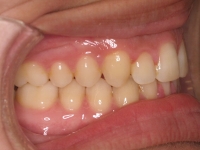

Premolar mandibular incluido + fenestración

Radiografía de final de tratamiento